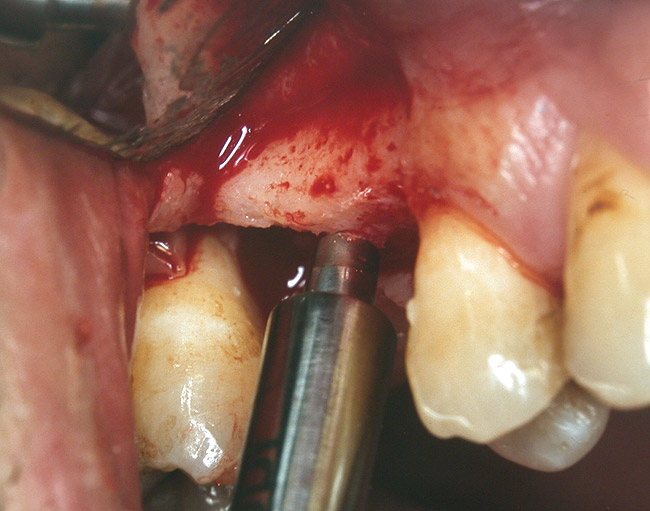

A full-thickness mucoperiosteal flap was raised, and alternating osteotomes were used to prepare the implant site. After achieving a length of 7 mm (Figure 7A and Figure 7B), heterologous bone graft was implanted and the osteotome sequence was repeated. The implant showed primary stability.

Figure 7A and Figure 7B Alternating osteotomes with variable conicity used to perform the alveolar remodeling in the area of tooth No. 15.

Figure 7a  Alternating osteotomes with variable conicity used to perform the alveolar remodeling in the area of tooth No. 15.

Figure 7a

Figure 7b  Alternating osteotomes with variable conicity used to perform the alveolar remodeling in the area of tooth No. 15.

Figure 7b